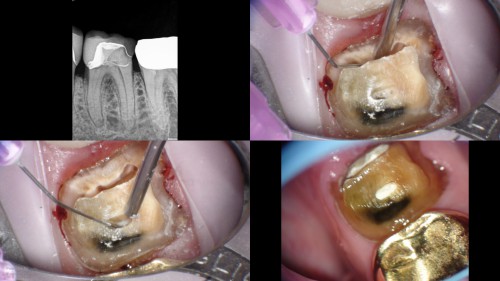

#19 Caries Driven access

By Reuben Joseph / July 17, 2018

Clinical Scenario and treatment done DO caries with a deep sub-gingival margin Resorbed apex – […]

#30 – Caries Driven Access

By Reuben Joseph / July 16, 2018

#30 Pulpitis. Caries involving the ML cusp. Caries driven access planned   Mb located in the middle […]